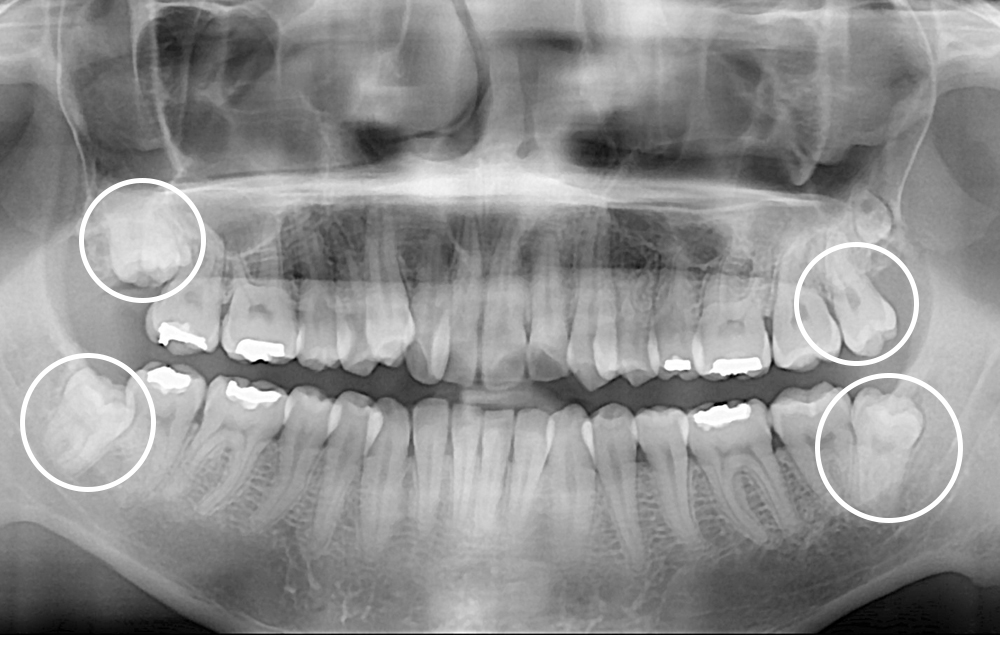

[사랑니] 매복 사랑니 발치

치료후 : 2020-05-11

세종치과는 구강악안면외과학 박사이신 원장님이 발치하는 치과입니다.